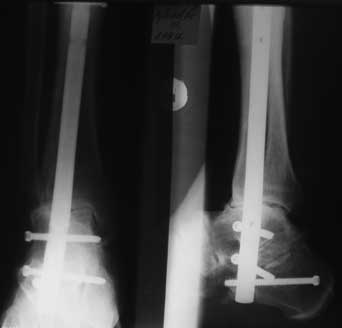

Взаимоисключающие требования, т.к. от боли его из бавит только

артродез, но он, соответственно, лишит движений. В приложении

- малоинвазивный компрессионный артродез с помощью БИОС.

Боли прошли сразу после операции.